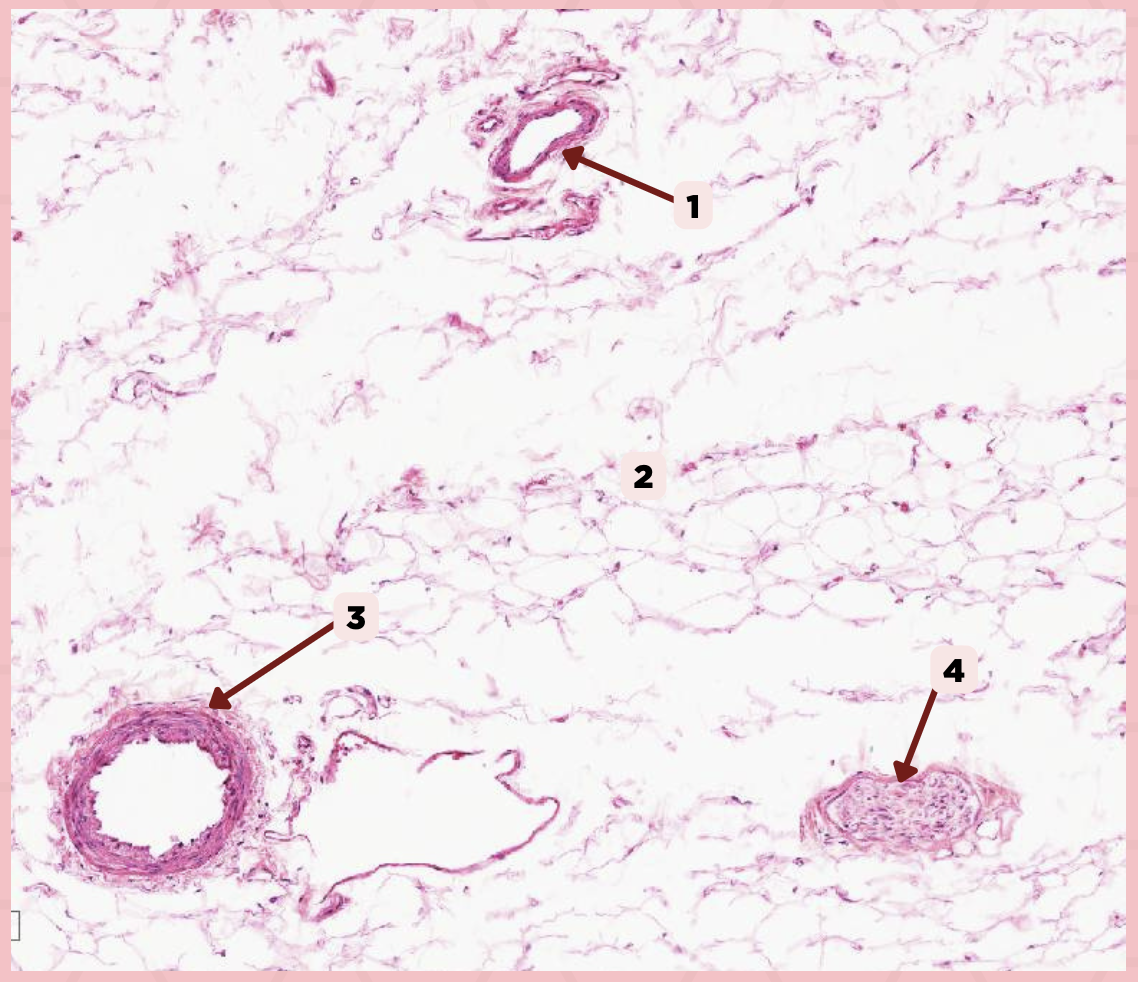

Cheek

Identify the specimen.

Vein

Identify the structure labeled as 1.

Hypodermis

Identify the structure labeled as 2.

Artery

Identify the structure labeled as 3.

Nerve

Identify the structure labeled as 4.